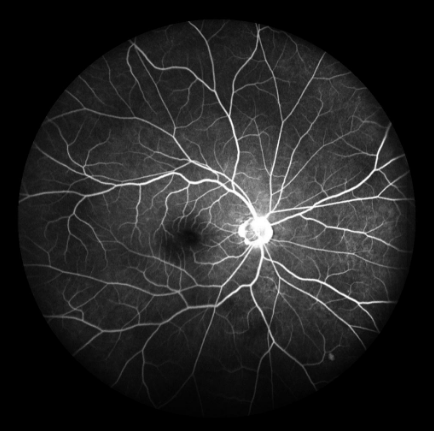

FFA是20世纪60年代发展的一项技术。1961年Navotny 和Alvis首次成功地用胶片记录到荧光素流经视网膜和脉络膜血管的动态过程,开创了眼底荧光血管造影的临床应用时代。如今,FFA主要用于观察视网膜血管及其血液循环状态,高清晰摄像技术能动态捕捉视网膜毛细血管的循环状态,间断或连续采集可形成视网膜静态的黑白图像或动态图像,在诊断中敏感性强,确诊率高,能发现检眼镜或眼底照相下不易发现的视网膜深层微血管瘤,是判断视网膜病变的“金标准”。

FFA影像